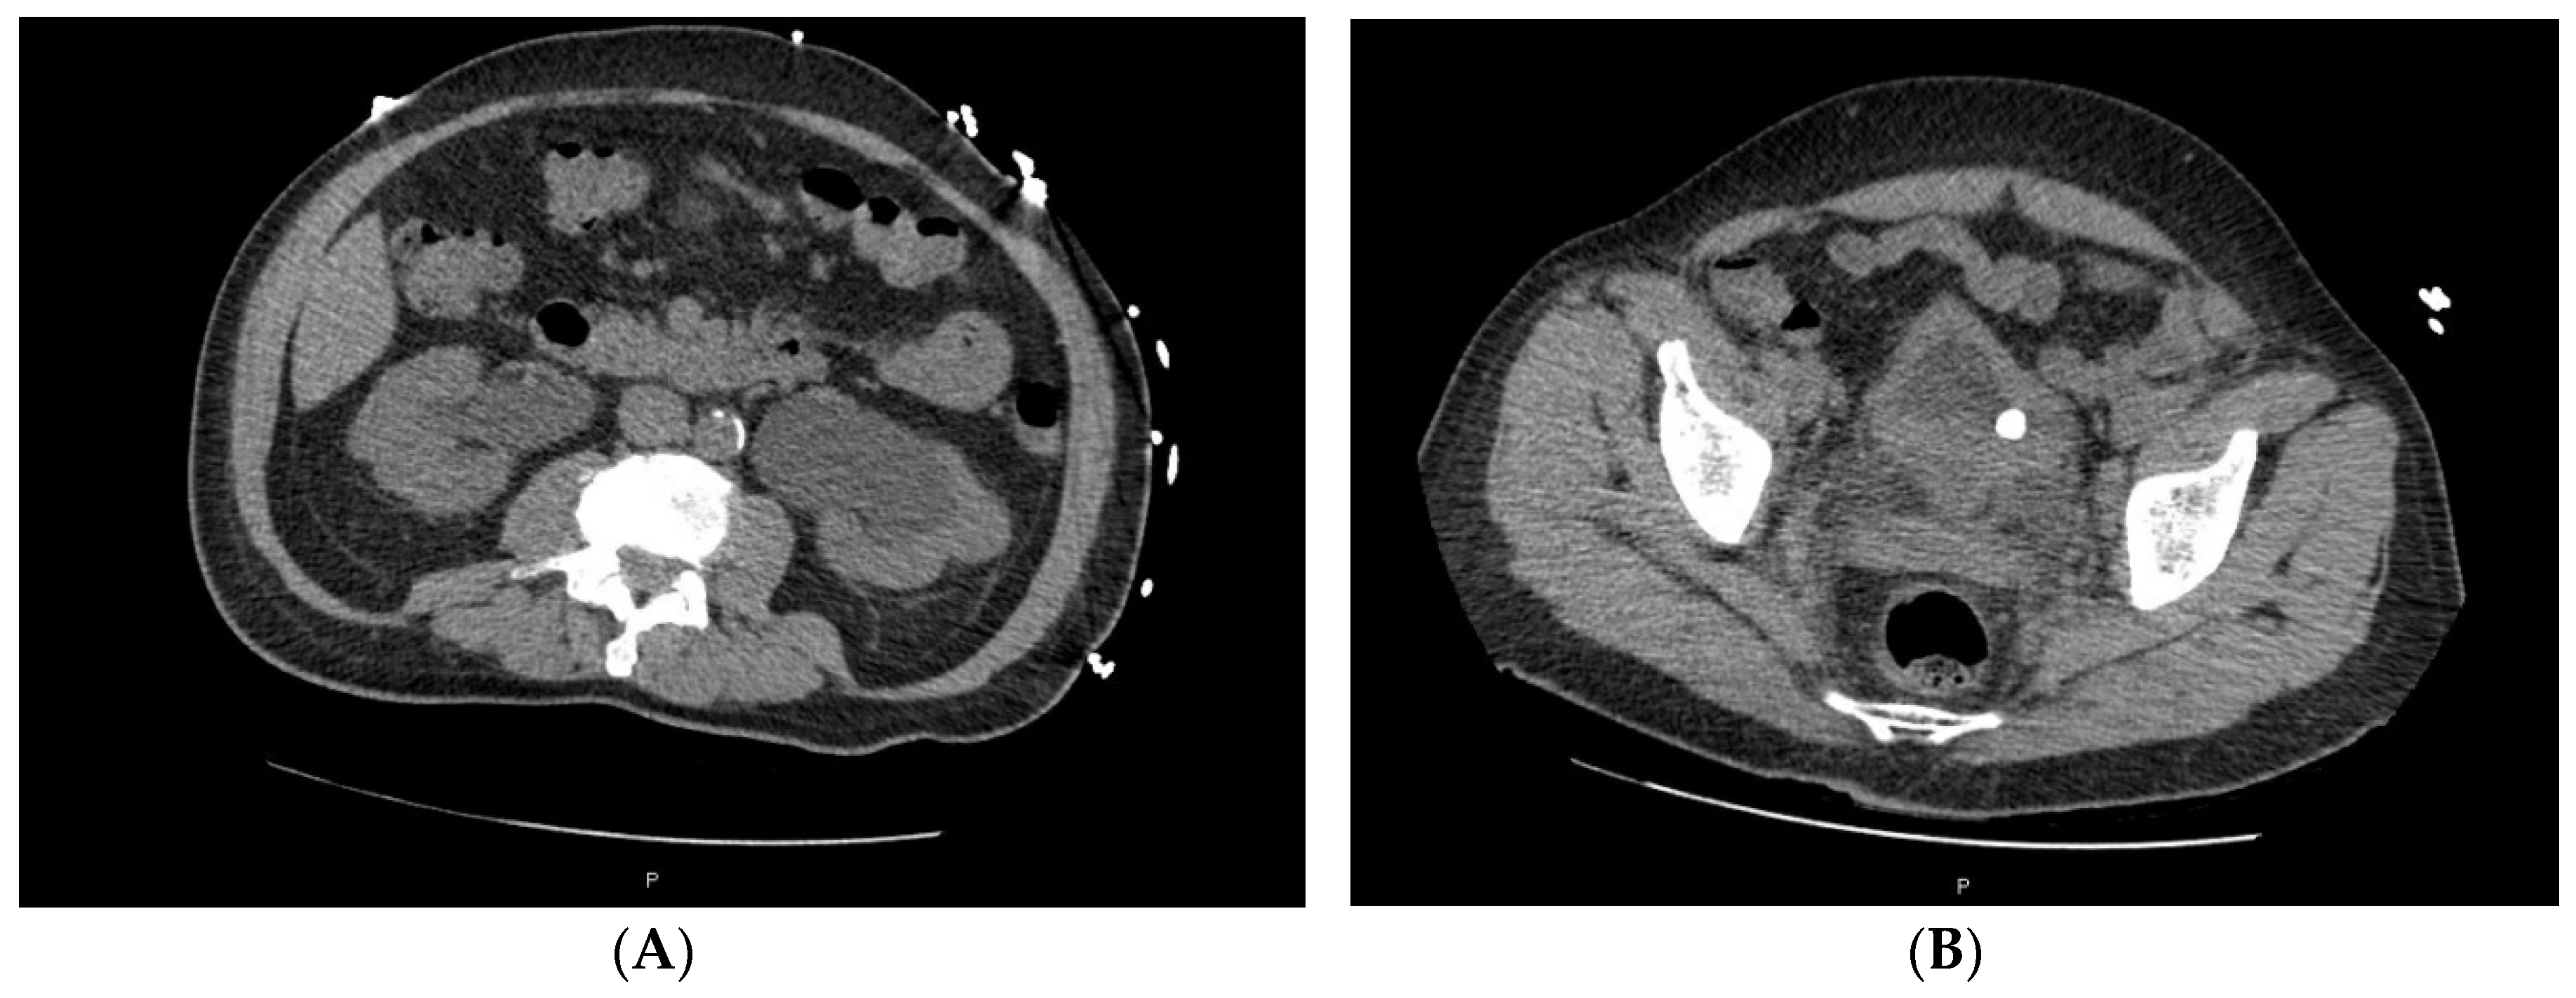

Figure 4.

Bladder thickening and hydronephrosis. (A) CT scan pre-cystectomy showing bilateral hydronephrosis for case 2; (B) CT scan shows bladder thickening for case 2 and calculi.

Case 2 is a 71 y/o male who presented with prostatic hyperplasia symptoms and acute renal insufficiency. Initial imaging showed bilateral hydronephrosis and bladder calcifications. He underwent TURP and TURBT, which revealed high-grade urothelial carcinoma with plasmacytoid and micropapillary features. CT staging showed a markedly thickened and nodular wall of the urinary bladder and calculus (Figure 4), which was consistent with bladder malignancy (suspicious for a diffuse infiltrating tumor) and an abnormal right ureteral dilation with wall thickening and enhancement suspicious for tumor involvement in the right ureter, as well as bilateral pelvic sidewall and retroperitoneal lymphadenopathy. He received chemotherapy with gemcitabine and cisplatin for six cycles with good partial response and ultimately underwent radical cystoprostatectomy, ileal diversion, and lymph node dissection with pathology that revealed high-grade urothelial carcinoma with a plasmacytic variant signet ring and micropapillary features with bulky residual disease pT4pN2Mx. Immunopathologic staining showed +CK20, p53, HER2+ IHC stains, negative PSA, and PD-L1 staining. Sequencing results showed ERBB2 amplification. However, he had ongoing gastrointestinal symptoms of nausea and vomiting, which led to further endoscopies that revealed peritoneal carcinomatosis. He received several cycles of pembrolizumab, and though initial symptom stabilization was seen, further progression ensued and hospice ultimately engaged.